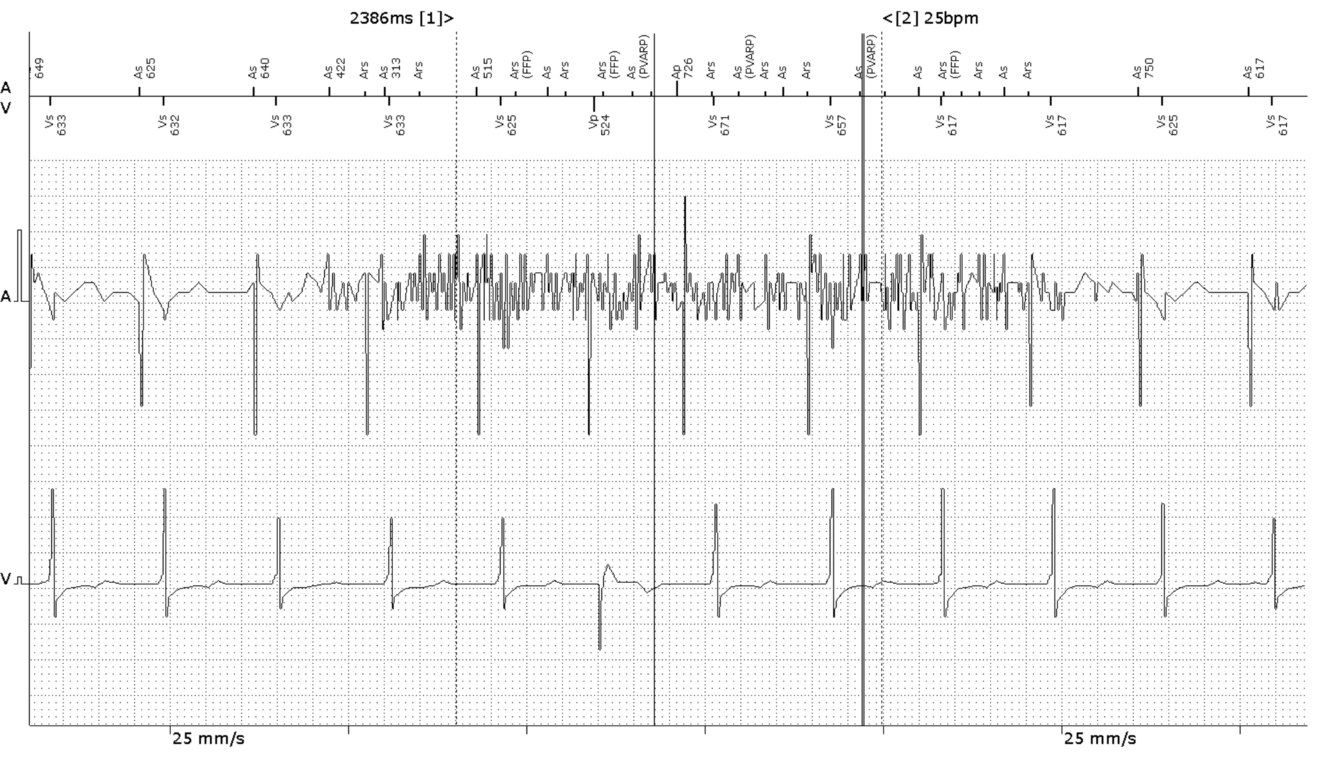

Would IRS+, MVP, VIP or RYTHMIQ be appropriate for this patient?

No.

These are all algorithms designed to reduce RV pacing. This patient has CHB as evidenced by 100% RVp. These algorithms would likely invoke symptoms.

Yes / No

Yes.

These algorithms aim to reduce RVp% by promoting intrinsic rhythm. This patient is clearly suitable for such treatment as 99% of V-events are sensed - thus evidencing intrinsic conduction.